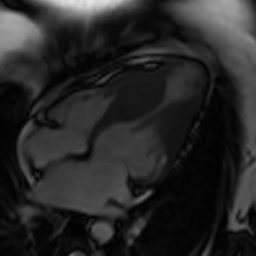

Non compattazione del VS

Dario Sansalone